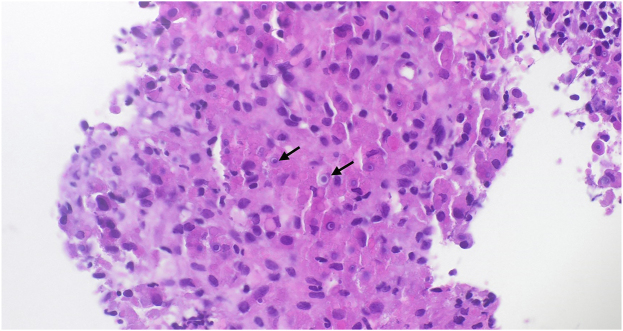

Prescottella (Rhodococcus) soli is a soil-dwelling organism not previously thought to be pathogenic in humans. We discuss the case of a 78-year-old male renal transplant recipient presenting with respiratory symptoms and multiple pulmonary nodules, found to be pulmonary malakoplakia secondary to infection with Prescottella (Rhodococcus) soli. Treatment was commenced with vancomycin, meropenem and azithromycin for an induction period of two weeks and continued with indefinite oral moxifloxacin and azithromycin with significant clinical improvement. Although rare, Prescottella species, including Prescottella soli, should be considered in the differential diagnosis of pulmonary nodules, particularly in immunocompromised patients. More data is required to inform optimal treatment.